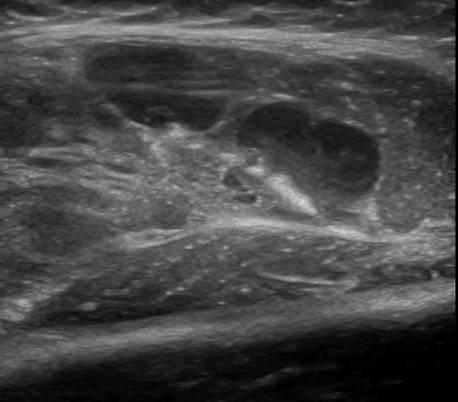

U xơ cơ

» Thông tin: Nữ giới – 3 tháng tuổi.

» Lâm sàng: Sưng vùng đùi.